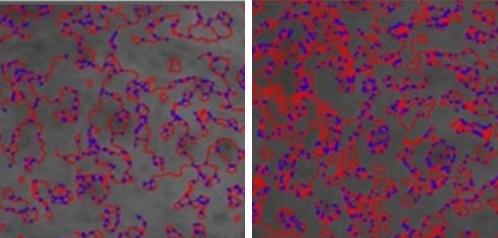

70% of Collagen Structure

Glycine, proline, and lysine account for approximately 70%

of the collagen structure. During fibroblast metabolic activity,

these amino acids stimulate fibroblasts to promote collagen

production and support collagen synthesis, helping improve

skin firmness and structural integrity.